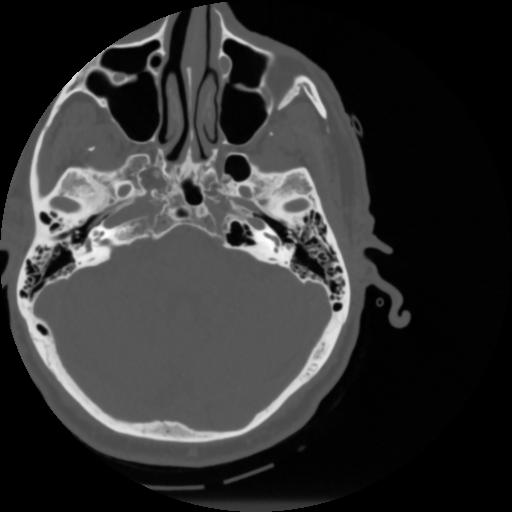

4 CEREBRO,,Vol,0.5,CEREBRO,,